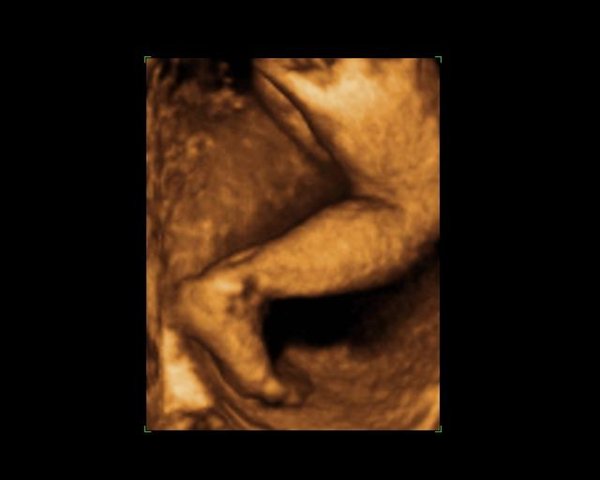

Dernæst havde vi bestilt tid til en privat 3d/4dscanning på scanningsklinikken i København, men den første gang lå hun med hænderne foran ansigtet, så vi blev tilbudt en ekstra gratis.. Det samme skete så anden gang igen og så var de så søde at vi fik en tredje gang, og så kunne vi endelig se hendes smukke ansigt